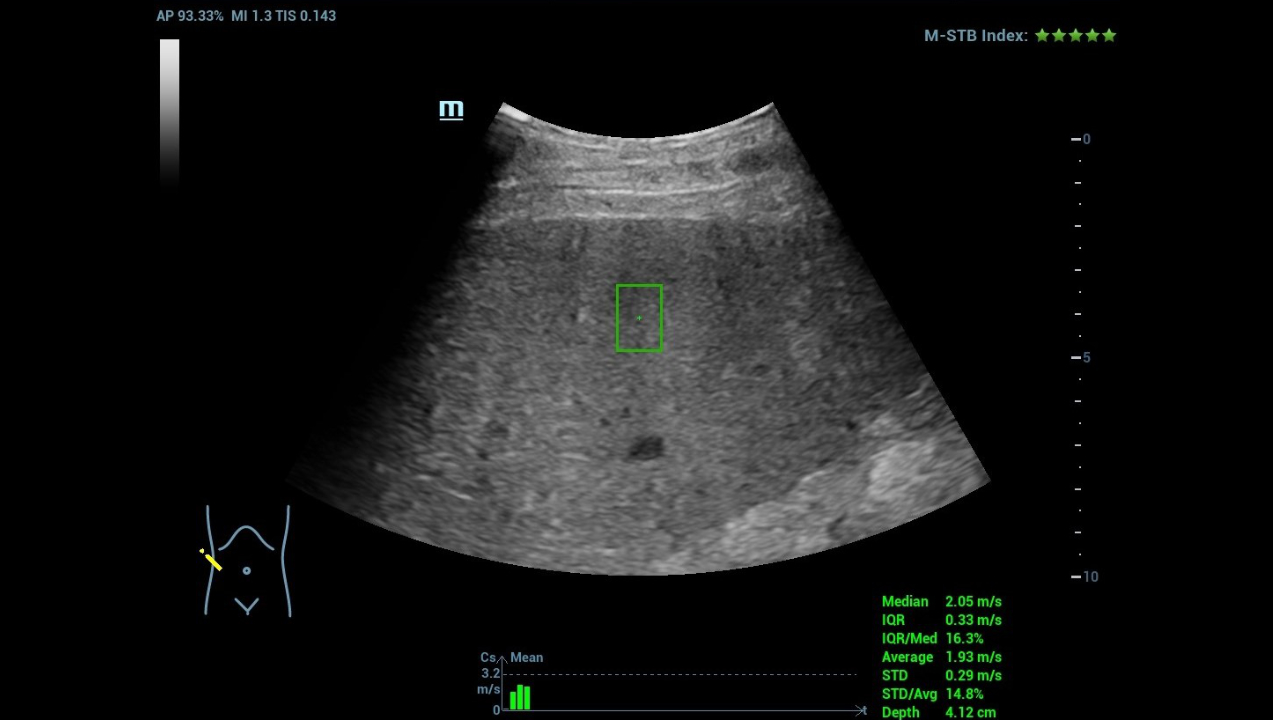

hifr-ceus-liver-fig4-pc

Sound Touch Quantification (STQ)

hifr-ceus-liver-fig5-pc